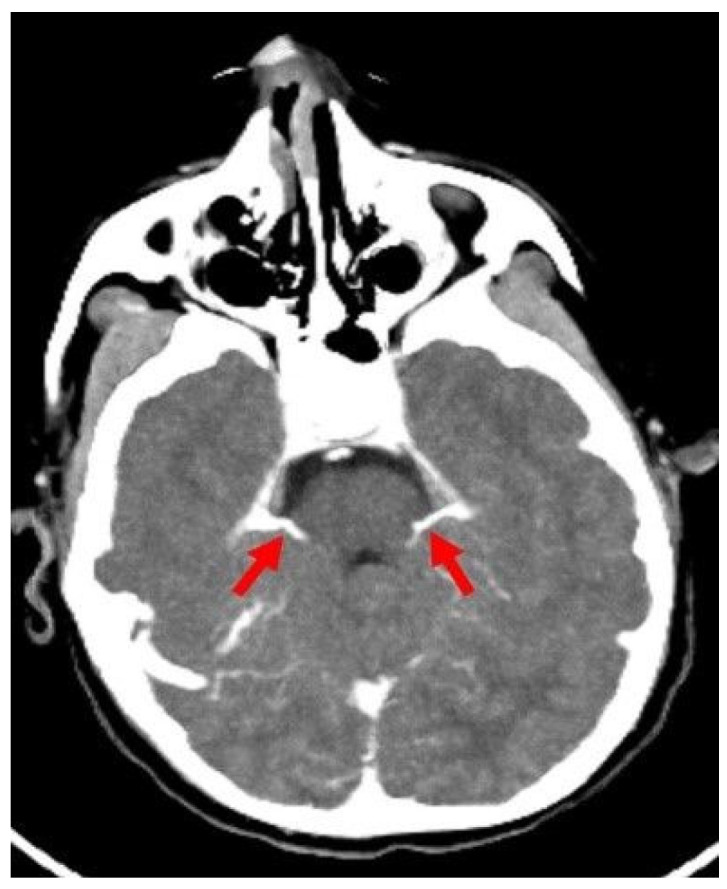

Background/objectives: While ancillary tests for brain death diagnosis are not routinely recommended in guidelines, they may be necessary in specific clinical scenarios. Computed tomography angiography (CTA) is particularly advantageous in pediatric patients due to its noninvasive nature, accessibility, and rapid provision of anatomical information. This study aims to assess the diagnostic sensitivity of a revised venous system (ICV-SPV) utilizing a 4-point scoring system in children clinically diagnosed with brain death.

Materials and methods: A total of 43 pediatric patients clinically diagnosed with brain death who underwent CTA were retrospectively analyzed. Imaging was performed using a standardized brain death protocol. Three distinct 4-point scoring systems (A20-V60, A60-V60, ICV-SPV) were utilized to assess vessel opacification in different imaging phases. To evaluate age-dependent sensitivity, patients were categorized into three age groups: 26 days-1 year, 2-6 years, and 6-18 years. The sensitivity of each 4-point scoring system in diagnosing brain death was calculated for all age groups.

Results: The revised venous scoring system (ICV-SPV) demonstrated the highest overall sensitivity in confirming brain death across all age groups, significantly outperforming the reference 4-point scoring systems. Furthermore, the ICV-SPV system exhibited the greatest sensitivity in patients with cranial defects.

Conclusions: The revised 4-point venous CTA scoring system, which relies on the absence of ICV and SPV opacification, is a reliable tool for confirming cerebral circulatory arrest in pediatric patients with clinical brain death.